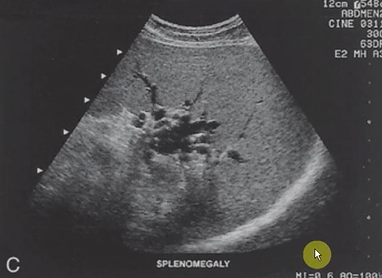

What are the sonographic findings with splenomegaly?

Superior to Inferior measurement > 13 cm

The inferior pole of the spleen covers the superior pole of the left kidney

Splenomegaly

What is the most common cause of splenomegaly?

Portal hypertension